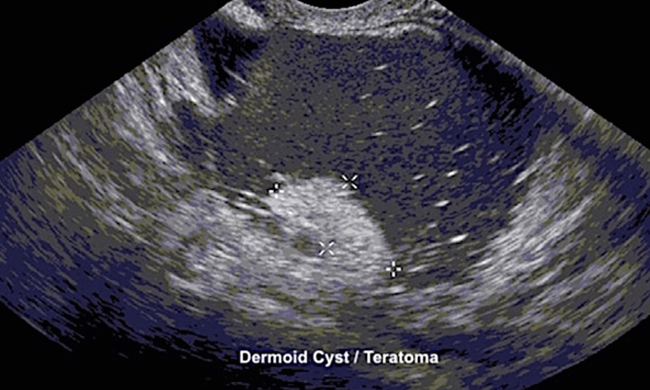

"Tissue Cysts" or Dermoid Cysts (or benign mature cystic teratomas) usually contain oily tissues and hair. Dermoid Cysts form because the ovary has cells that can develop into any type of body tissue. Hence, these cysts often contain skin, fat, bone and cartilage. Dermoid cysts can happen in both ovaries 10% of the time.